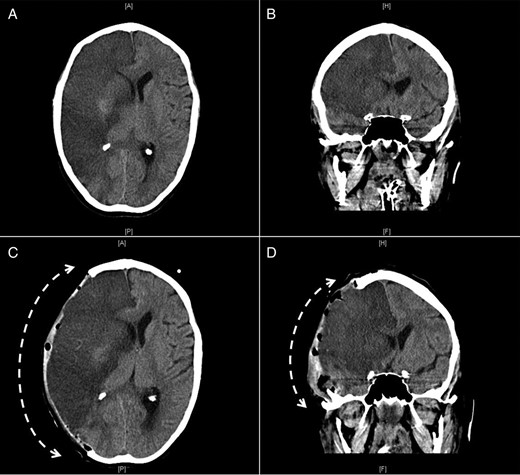

Transthoracic echocardiogram (TTE) revealed a 4.8 × 2.5 cm mobile mass arising from the interatrial septum of a severely dilated left atrium, causing moderate left ventricular inflow obstruction with a mean gradient of 12 mmHg and trace mitral regurgitation (Fig. 1A and B). There was severe tricuspid regurgitation with a systolic pulmonary artery pressure of 61 mmHg. The patient described symptoms of angina before her current hospitalization for shortness of breath. For that reason, a coronary angiogram was ordered before her surgery and revealed 80% lesions in the mid-left anterior descending artery and a 70% stenosis at the origin of the posterior descending artery of a dominant left circumflex artery.

TTE 4-chamber view during systole (A) and diastole (B) showing a large LAM attached to the interatrial septum and obstructing diastolic filling of the left ventricle and follow-up four-chamber view during systole (C) and diastole (D) showing a marked reduction in the size of the LAM (LA, left atrium; LV, left ventricle; RA, right atrium; RV, right ventricle).

The next morning after her coronary angiogram, the patient suddenly showed signs of confusion and began to experience slurred speech and left-sided facial droop with left-sided hemiplegia. She was intubated to protect the airway and was sent for an urgent computed tomography (CT) scan of the head, which revealed a hyperdense minute clot lodged at the right internal carotid artery bifurcation. Accordingly, tissue plasminogen activator thrombolytic therapy was initiated. A repeat TTE showed that the mass was markedly decreased in size (2.1 × 0.9 cm) compared with a previous study, likely due to embolization (Fig. 1C and D).